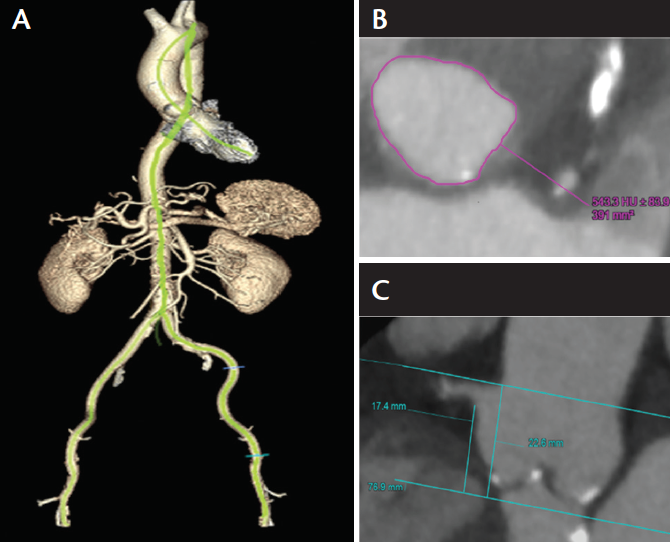

TAVR was successfully performed with a 23-mm, balloon-expandable transcatheter heart valve (THV; Sapien 3, Edwards Lifesciences) via TF access, which provided 3.8% oversizing. The patient was extubated in the hybrid operating room immediately postprocedure with no complications. On postoperative day 1, TTE revealed a well-seated THV with a mean TVG of 17 mm Hg, an aortic velocity of 2.7 m/s, and no evidence of aortic insufficiency. The patient was discharged on postoperative day 2. The patient returned for follow-up 1 year after TAVR without cardiac symptoms or limitations (NYHA class I) and a sustained improvement in his functional capacity. At 1 year, TTE demonstrated a left ventricular ejection fraction of 75%, a mean TVG of 12 mm Hg, an aortic velocity of 2.3 m/s, and no evidence of aortic insufficiency (Figure 2).